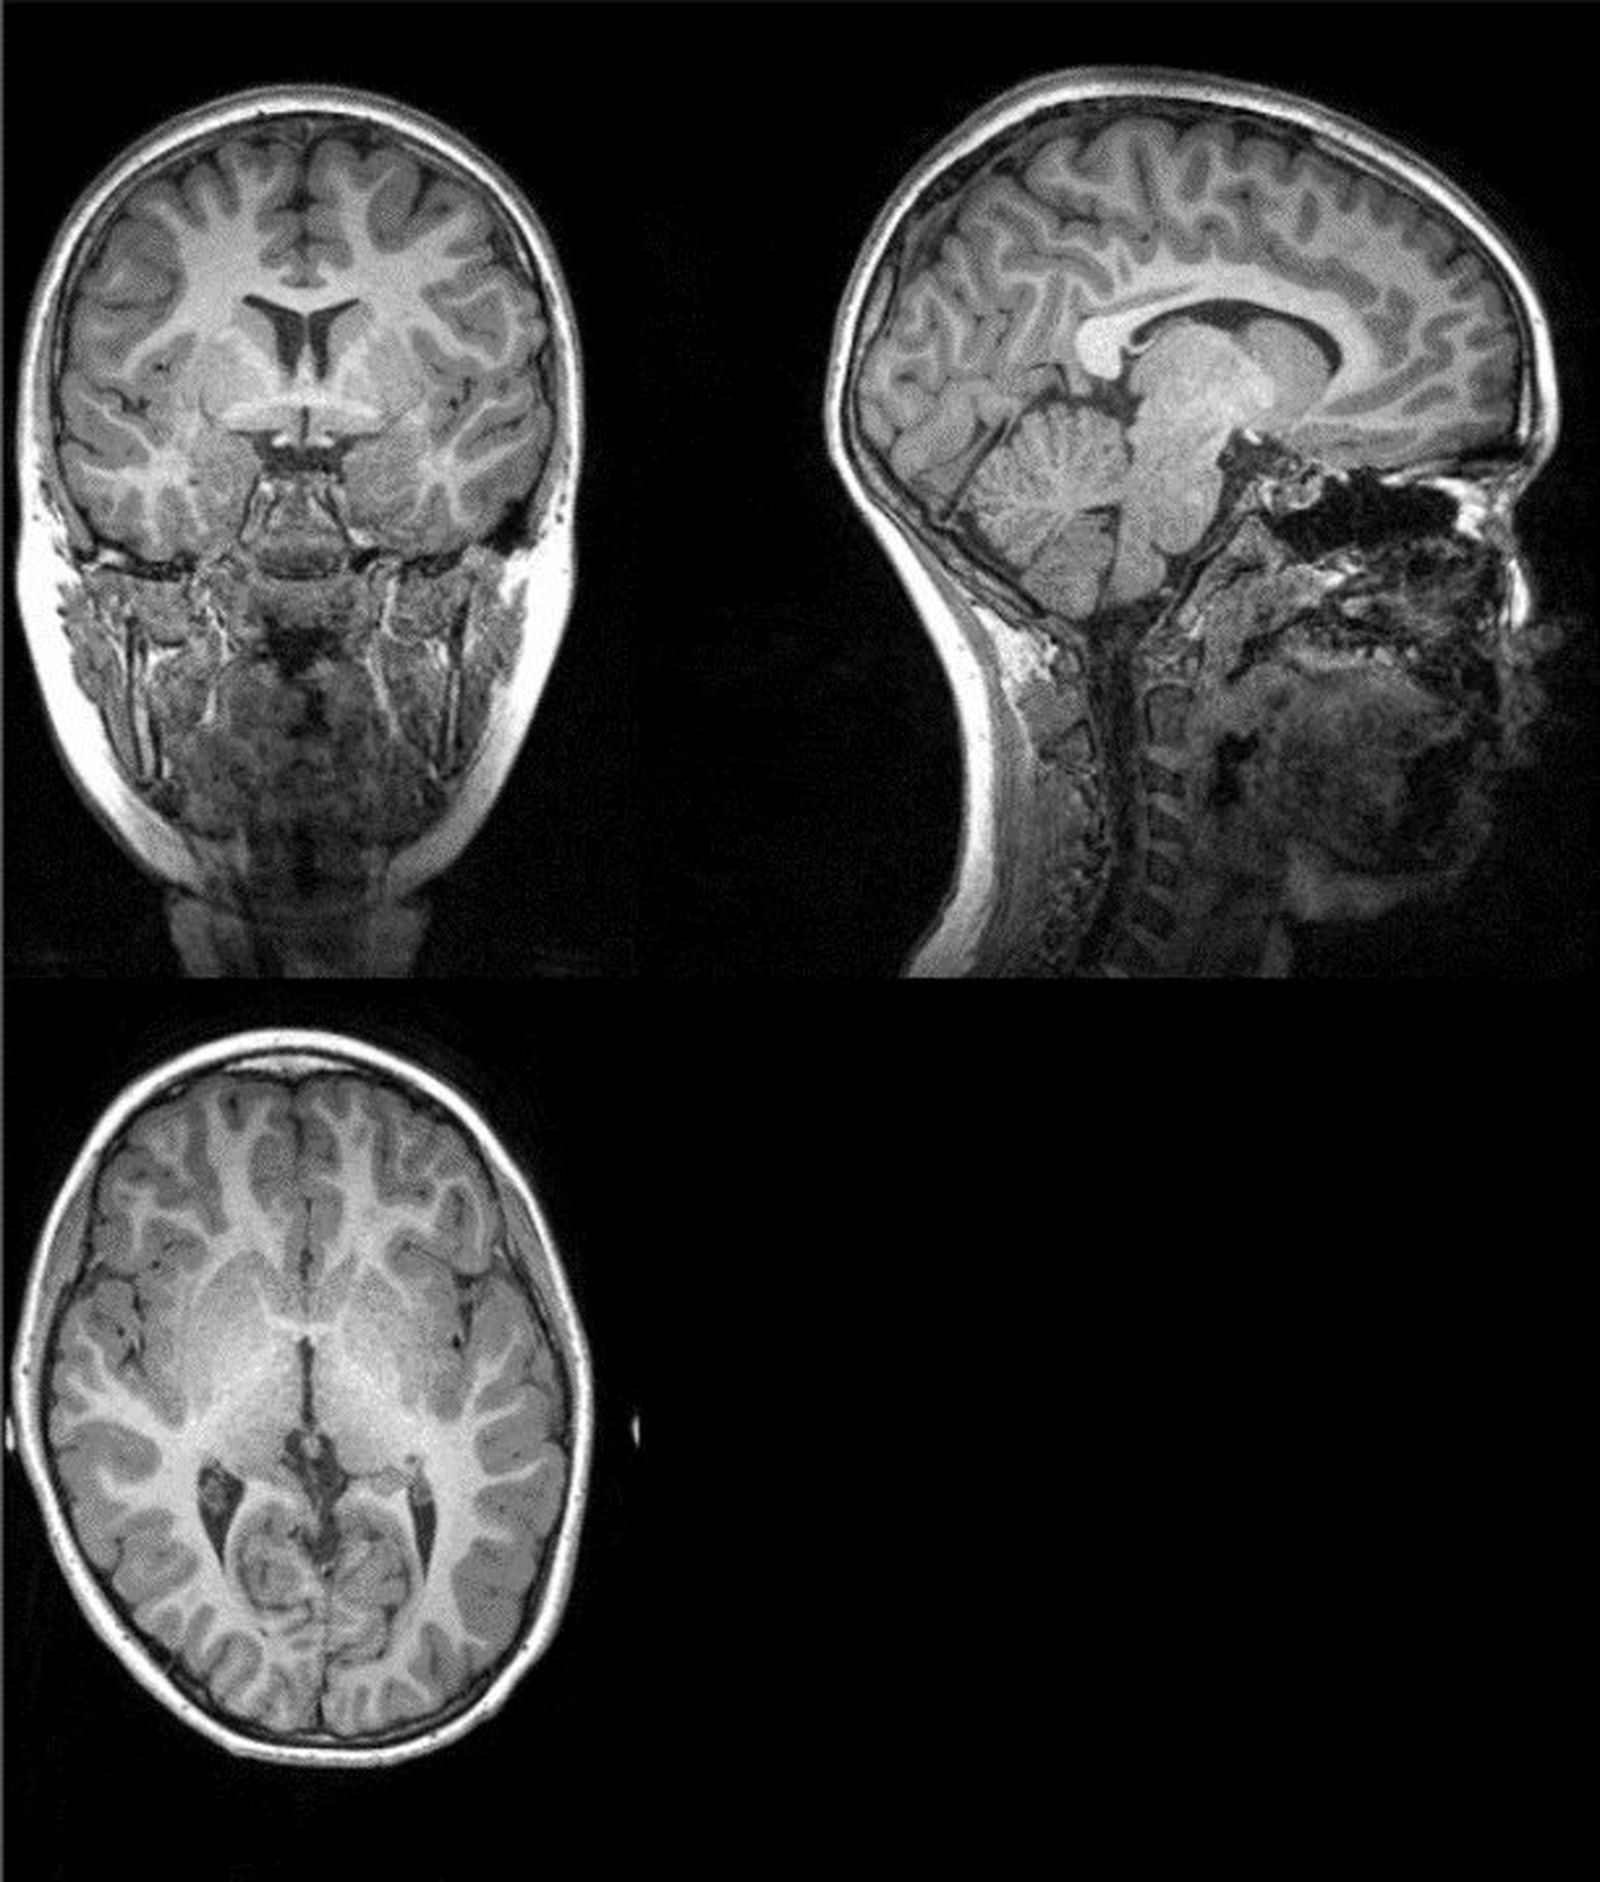

Ejemplo de imagen original de la resonancia magnética a partir de la cual los investigadores extrajeron la cantidad total de materia gris, materia blanca, y cantidad total cerebral.

Ejemplo de imagen original de la resonancia magnética a partir de la cual los investigadores extrajeron la cantidad total de materia gris, materia blanca, y cantidad total cerebral. / R. G.

Este trabajo, publicado en la revista Scandinavian Journal of Medicine &Science in Sports, revela que los niños que fueron clasificados como “en forma” tenían mayor cantidad de materia gris, materia blanca, y en general, cerebros más grandes que aquellos niños que fueron agrupados como “en baja forma”. Asimismo, tener más materia blanca en el cerebro estaba relacionado con un mayor rendimiento cognitivo, concretamente, mayor flexibilidad cognitiva y función ejecutiva.